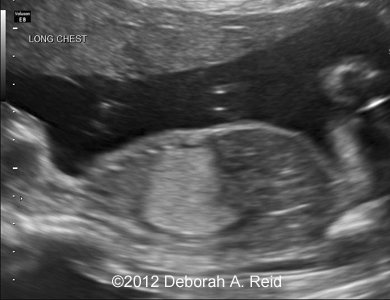

Ultrasound showed left-sided congenital diaphragmatic hernia with mild polyhydramnios.

The left-sided congenital diaphragmatic hernia contained a large portion of the bowel, spleen, stomach and the tip of the left lobe of the liver. In addition to the congenital diaphragmatic hernia, a sub-diaphragmatic sequestration was also noted which was confirmed by MRI.

Figure 1-10: The left-sided congenital diaphragmatic hernia contained a large portion of the bowel, spleen, stomach and the tip of the left lobe of the liver